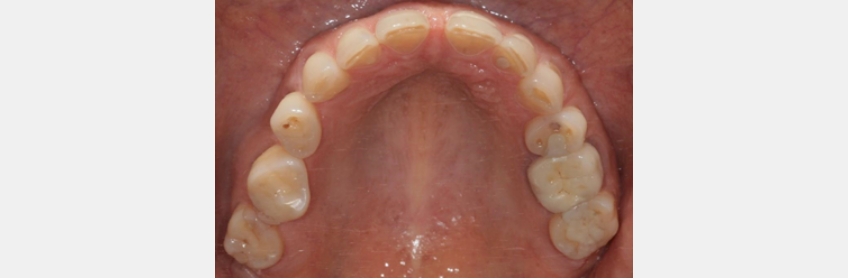

Recent studies in the otolaryngology literature are providing dentists with support for a new paradigm. The newest research shows that a narrow, highly vaulted maxilla in the premolar region increases the risk of having obstructive apnea.

In a separate study, it was determined that a narrow maxilla creates palatal or base tongue collapse. Further, the location of the narrowing is linked to different types of blockages: Molar narrowing creates different obstructive points than premolar narrowing. Lastly, if the maxilla is expanded, the airway collapse is reduced significantly.